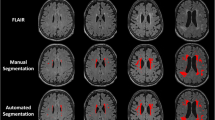

Brain tissue segmentation (gray matter, white matter, and cerebrospinal fluid) of the skull-stripped T1-weighted MRI was generated via Atropos (Avants et al. 2011). The label map was further parcellated into the regions defined by the SRI24 atlas (Rohlfing et al. 2010) by non-rigidly registering the atlas to the MRI via ANTS (Avants et al. 2008). Frontal gray matter was parcellated into seven regions of interest: precentral, superior, orbital, middle, inferior, supplemental motor, and medial (Fig. 1). Based on our hypotheses we also measured the hippocampus and thalamus. Brain volumes were age- and head-sized corrected based on 238 control participants (19–86 years). Automatic labeling was always visually inspected for accuracy by a trained research scientist.